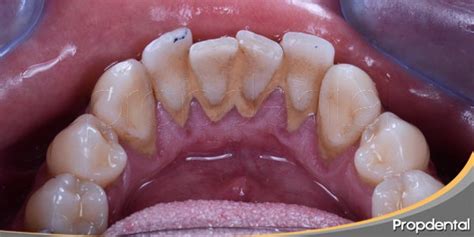

¿Dónde se Acumula Preferentemente el Sarro?

- El sarro se acumula preferentemente en los dientes inferiores debido a su proximidad a las glándulas salivales sublinguales y submandibulares, que secretan minerales directamente hacia esta zona.

- La superficie lingual de los dientes inferiores representa una de las zonas más desafiantes para mantener una higiene bucal adecuada. La posición de la lengua, la limitada visibilidad durante el cepillado y la dificultad para maniobrar el cepillo en esta área contribuyen a una limpieza incompleta.

- Muchas personas concentran sus esfuerzos de higiene bucal en las superficies dentales más visibles, descuidando inadvertidamente las zonas posteriores y linguales.

- El sarro se encuentra debajo de las encías, extendiéndose por la raíz del diente. Las encías suelen ser las más perjudicadas. Se ubica por debajo de la línea de la encía, focalizándose a su vez en la raíz del diente, siendo poco visible lo que hace que sea más dañino.